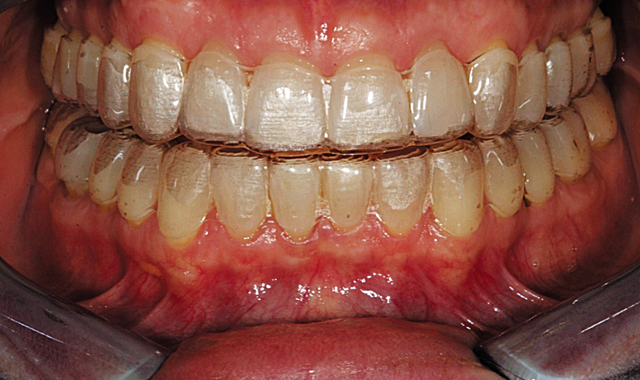

Our Invisalign treatment led to a very successful clinical result. The crowding and the asymmetries of tooth position, arch form and gingival levels were beautifully corrected (Figs. 14-16).

Fig. 14

Fig. 15

Fig. 16